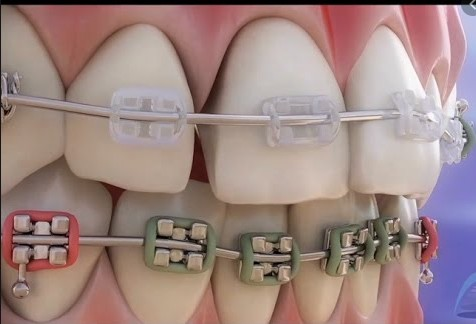

- Orthodontics or braces is a branch of dentistry that focuses on

correcting a patient’s teeth and jaw structure to improve the overall smile.

Dental issues such as crowded or crooked teeth can cause problems with smiling, chewing, and overall health.

Misaligned teeth also place excess pressure on other teeth, gums, and jaw joints, which can lead to conditions

like TMD and severe migraines.

Traditional braces consist of brackets that are bonded to each tooth, using a special dental adhesive,

and wires to help reposition the teeth. Braces are still the standard of care for treating significant

bite problems. Most younger teens prefer a stainless steel bracket that they can decorate with their

favorite colored o-rings that hold the wire to the bracket. We also offer ceramic brackets which are

virtually invisible and are the choice of many adult patients and older teens.

Traditional braces straighten the teeth by moving them with the help of a wire and elastics,

which look like tiny rubber bands. With these braces, you and your teen must periodically visit

Traditional braces work best for individuals who have severely crooked teeth or bite misalignments,

like crossbites, overbites and underbites. They also require less self discipline than aligner treatments.

Pros of Traditional Braces

Corrects Severely Crooked Teeth and Bite Misalignments

Most Affordable Teeth Straightening Option

Very Accurate

Multiple Bracket like ceramic, gold ,resin and self ligating brackets are available.

Does certain types of movements superiorly to aligners

Cons of Traditional Braces

Brackets Can Come Off Teeth

Certain Foods Must Be Limited or Avoided

Requires Strict Oral Hygiene Routine

Wire Adjustments Can Lead to Temporary Mouth Pain